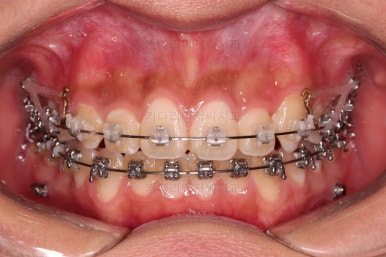

장치를 처음 부착했고요.

이번 환자분이 선택한 장치는 윗니는 세라믹 자가결찰인 엠파워 클리어, 아래는 메탈 자가결찰인 엠파워 메탈입니다. 둘 다 같은 회사의 같은 세팅의 장치이므로 혼용이 가능하죠. 대신 비용은 좀 더 줄일 수 있습니다.

초기 6개월 이내에 어느 정도 치열이 가지런해 졌네요.

중간평가 들어갑니다.

앞니가 많이 뻗쳤나요?

그렇지 않죠.

대신 처음에는 삐뚤어서 가려져 있던 부정교합이 드러나면서 최소한 윗니는 교합을 위해 후방이동이 필요한 상황이긴 했습니다.